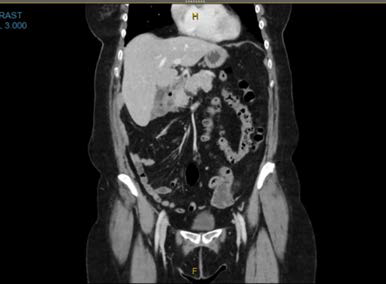

Pancreatic Transplant Jejunitis Complication: A Case Report

Ishan Gupta, Zachary Schmidt, Evelyn Kue, Imtiaz Ahmed, MD

1-7

PDF